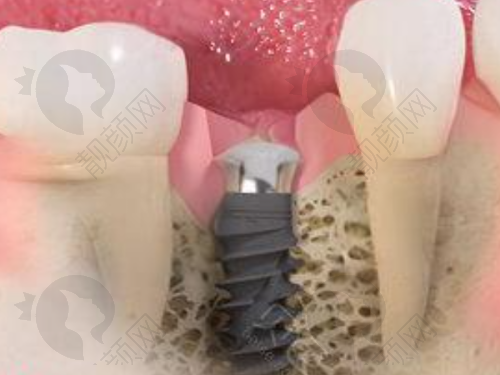

刘伟德医生在种植牙领域的水平十分出色。他毕业于北京医 科 大学口腔医学校,毕业后一直在大连医 科 大学附属二院从事口腔内科的临床和教学工作。多年的临床实践让他积累了丰富的经验,尤其在种植牙方面有深入的研究。

他精通种植牙的各种技术,能够根据患者的口腔状况、身体条件等因素,制定个性化的种植方案。在种植过程中,他操作精细、技术娴熟,能够较大程度地减少患者的痛苦,提高种植的成功几率。而且,他会在术后为患者提供详细的护理指导,确保种植成效的长期稳定。

他擅长牙体牙髓病、根尖病的治疗,各种牙体缺损和牙列缺失的修复,尤其是在根管治疗、牙体缺损的修复和种植牙方面有一定研究。凭借出色的专精能力和敬业精神,他成为了大连医 科 大学附属第二医院口腔科的骨干医生,深受患者和同事的好评。